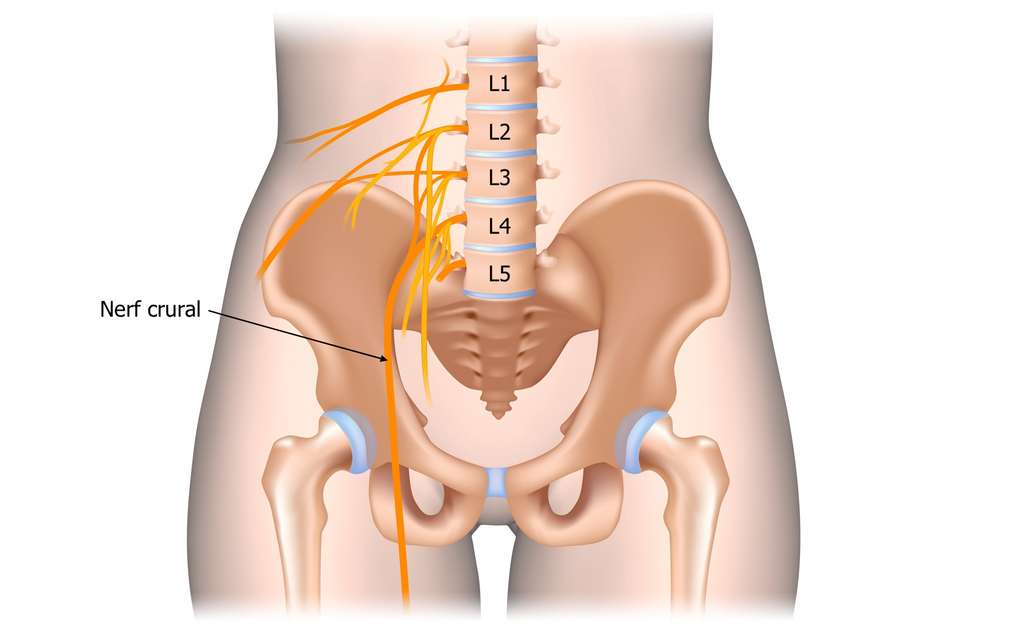

Le crural nerve, now called femoral nerve, is a nerve rooted in the spinal cord, at the level of the second, third and fourth vertebrae lumbar (L2, L3 and L4).

This nerve innervates the lower back, the thigh, the knee, the back of the calf, the ankle to the foot.